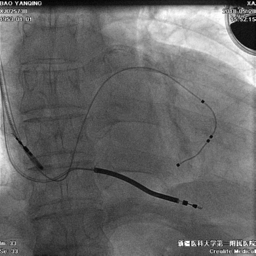

冠状静脉造影

● 通过长鞘造影,先冒烟,确认无夹层,造影后发现侧静脉分支,但不清楚远端情况。

鞘中鞘超选靶血管

● 使用鞘中鞘超选入靶血管

鞘中鞘造影

● 由于入口处有夹角,鞘中鞘无法深入,无论换用90还是130的鞘中鞘,开口处造影都看不到远端血管情况。

尝试导丝送入靶血管远端

● 尝试导丝先行,能否走到靶血管远端。

电极植入

● 延PTCA导丝送入电极至远端。